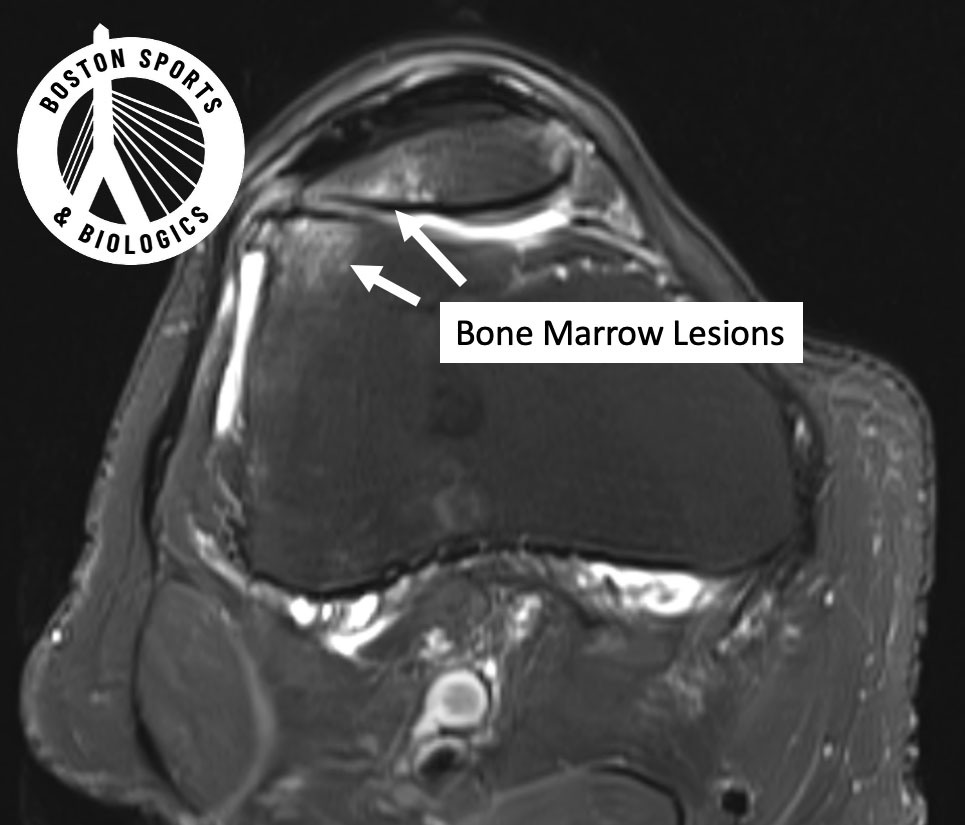

Advanced imaging studies show that bone marrow lesions (BMLs) — areas of stress and inflammation inside the bone — are strongly linked to pain progression and structural damage. Learn more about bone marrow lesions here.

MRI Findings

Subchondral injections led to:

Regression of bone marrow lesions

Reduction in synovitis

Preservation (and slight increase) in cartilage volume

Intra-articular injections:

Did not reduce bone marrow lesions

Showed worsening synovitis

Showed continued cartilage loss